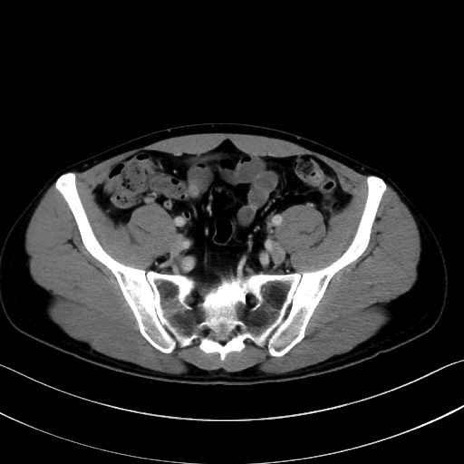

2. 腸腰筋群と骨盤底筋

大腰筋 (Psoas major)

腸骨筋 (Iliacus)